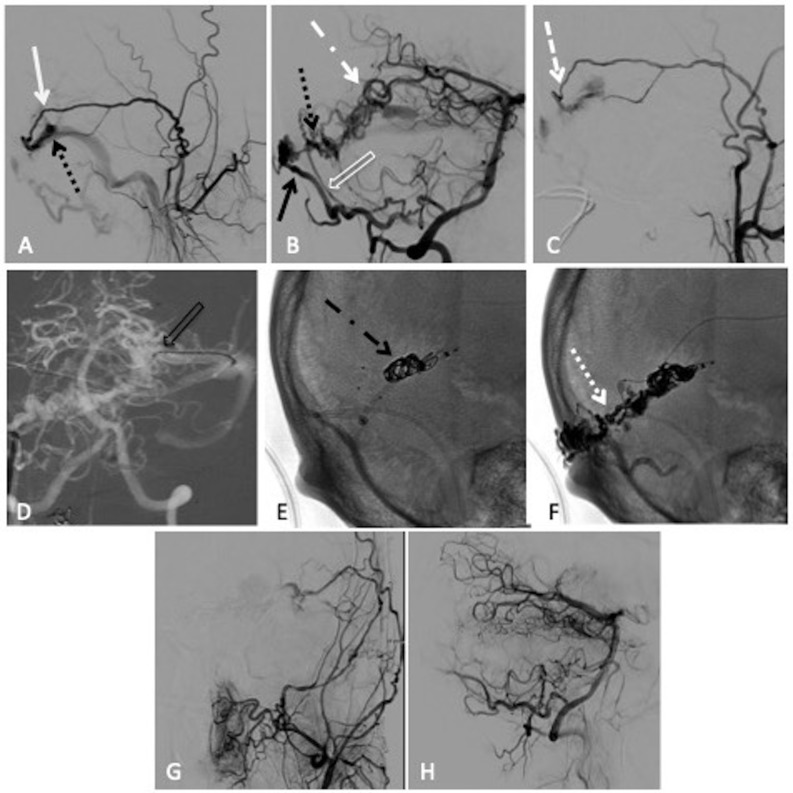

Figure 2.

Combined transarterial and transvenous embolisation of a left transverse sinus dural arteriovenous fistula (dAVF) with Onyx and microcoils. (A) Lateral projection pre-embolisation angiogram, selective left external carotid artery (ECA) injection and (B) right vertebral artery (VA) injection showing multiple arterial feeders arising from the left middle meningeal artery (MMA) (solid white arrow), right occipital artery (solid black arrow), right posterior meningeal artery (clear white arrow) and left artery of Davidoff and Schechter (dotted white dashed arrow), draining into a common channel (dotted black arrow). (C) Left ECA injection showing Scepter XC 4×11 mm microcatheter positioned within the MMA (dashed white arrow). (D) Anteroposterior (AP) road map showing Echelon 14 microcatheter positioned through the left transverse sinus and within the venous pouch (clear black arrow). Unsubtracted lateral view, (E) showing successful deployment of microcoils within the venous pouch (dotted black dashed arrow), (F) showing the Onyx cast after successful infusion through the MMA (dotted white arrow). Postembolisation lateral angiogram, (G) right VA injection and (H) left common carotid artery injection showing no residual dAVF.